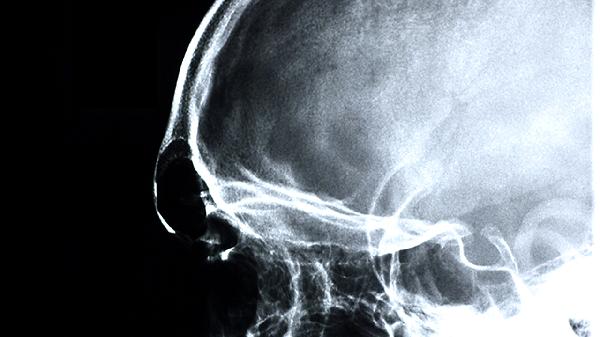

治疗脑供血不足可通过调整生活方式、控制基础疾病、药物治疗、手术治疗及康复训练等方式改善。脑供血不足通常由动脉粥样硬化、高血压、颈椎病等因素引起,表现为头晕、头痛、视物模糊等症状。